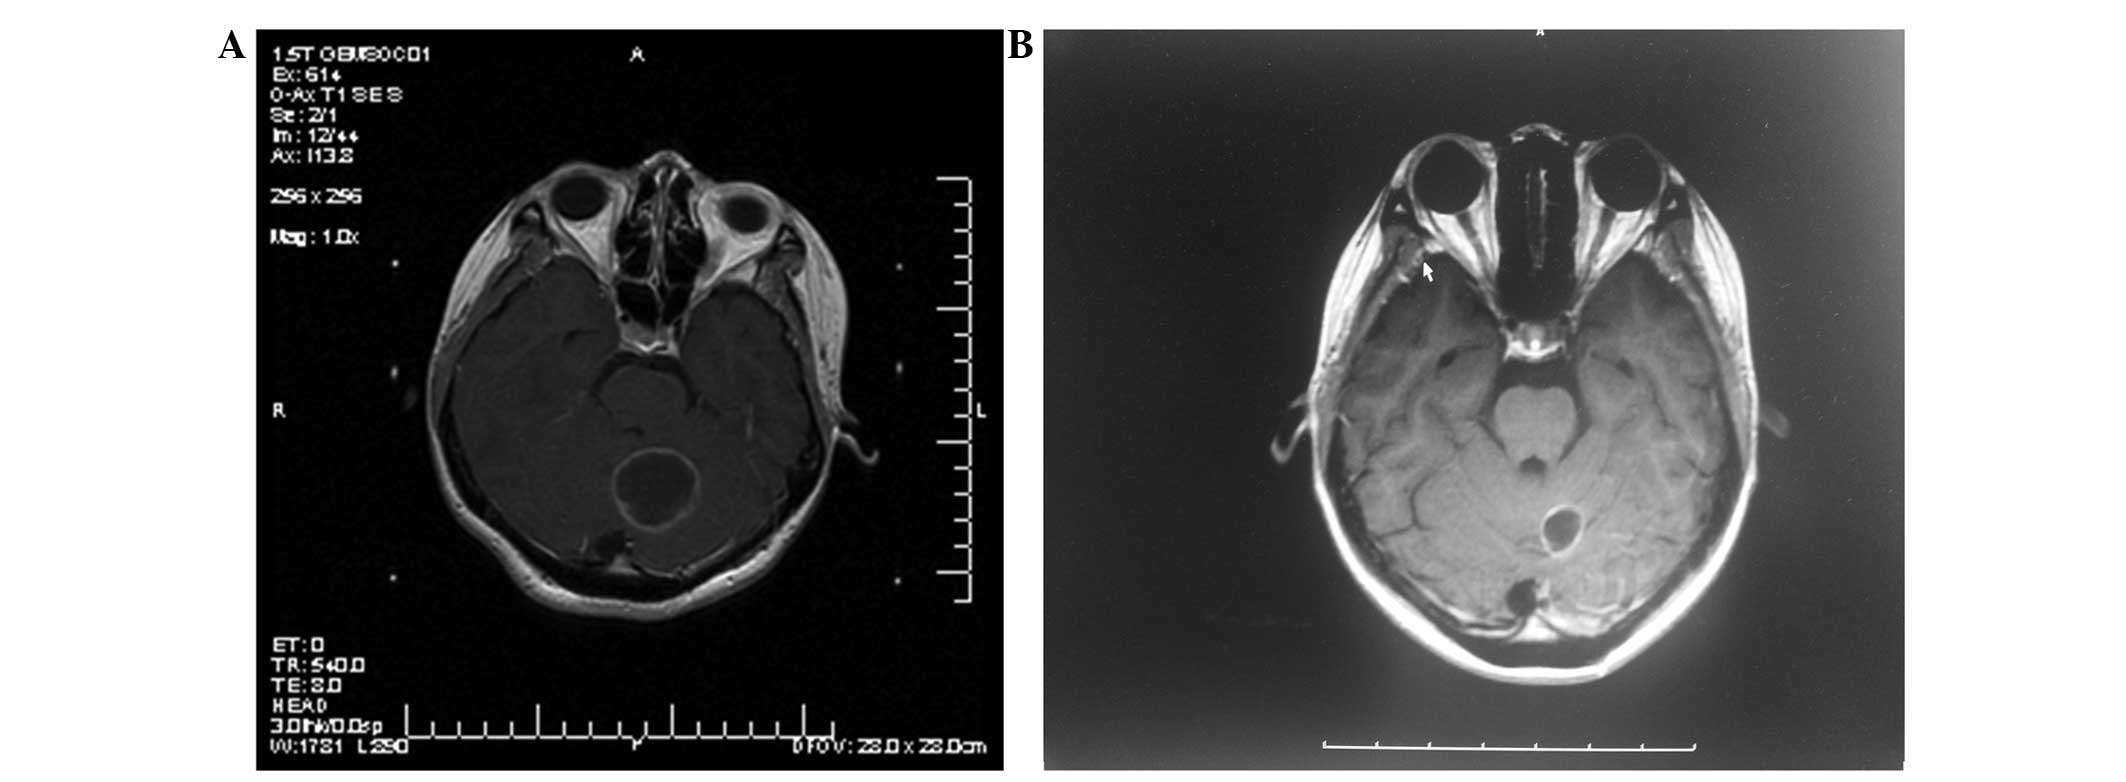

MRI was performed again after an interval of 3 months (Figs. 1 and 2). Tumor control was represented as a decrease in the tumor size following treatment. Progression of the local tumor was represented as an increase in size of the previously treated tumor. Moreover, the progression of the remote tumor was represented as the appearance of new brain metastases.

Figure 2.

T1-weighted (axial contrast-enhanced) magnetic resonance imaging of a 45-year-old man diagnosed with a large cystic brain metastasis. The prescribed dose of Gamma Knife radiosurgery (GKRS) was 18 Gy. (A) Prior to aspiration. (B) Subsequent to aspiration at 3 months post-GKRS.